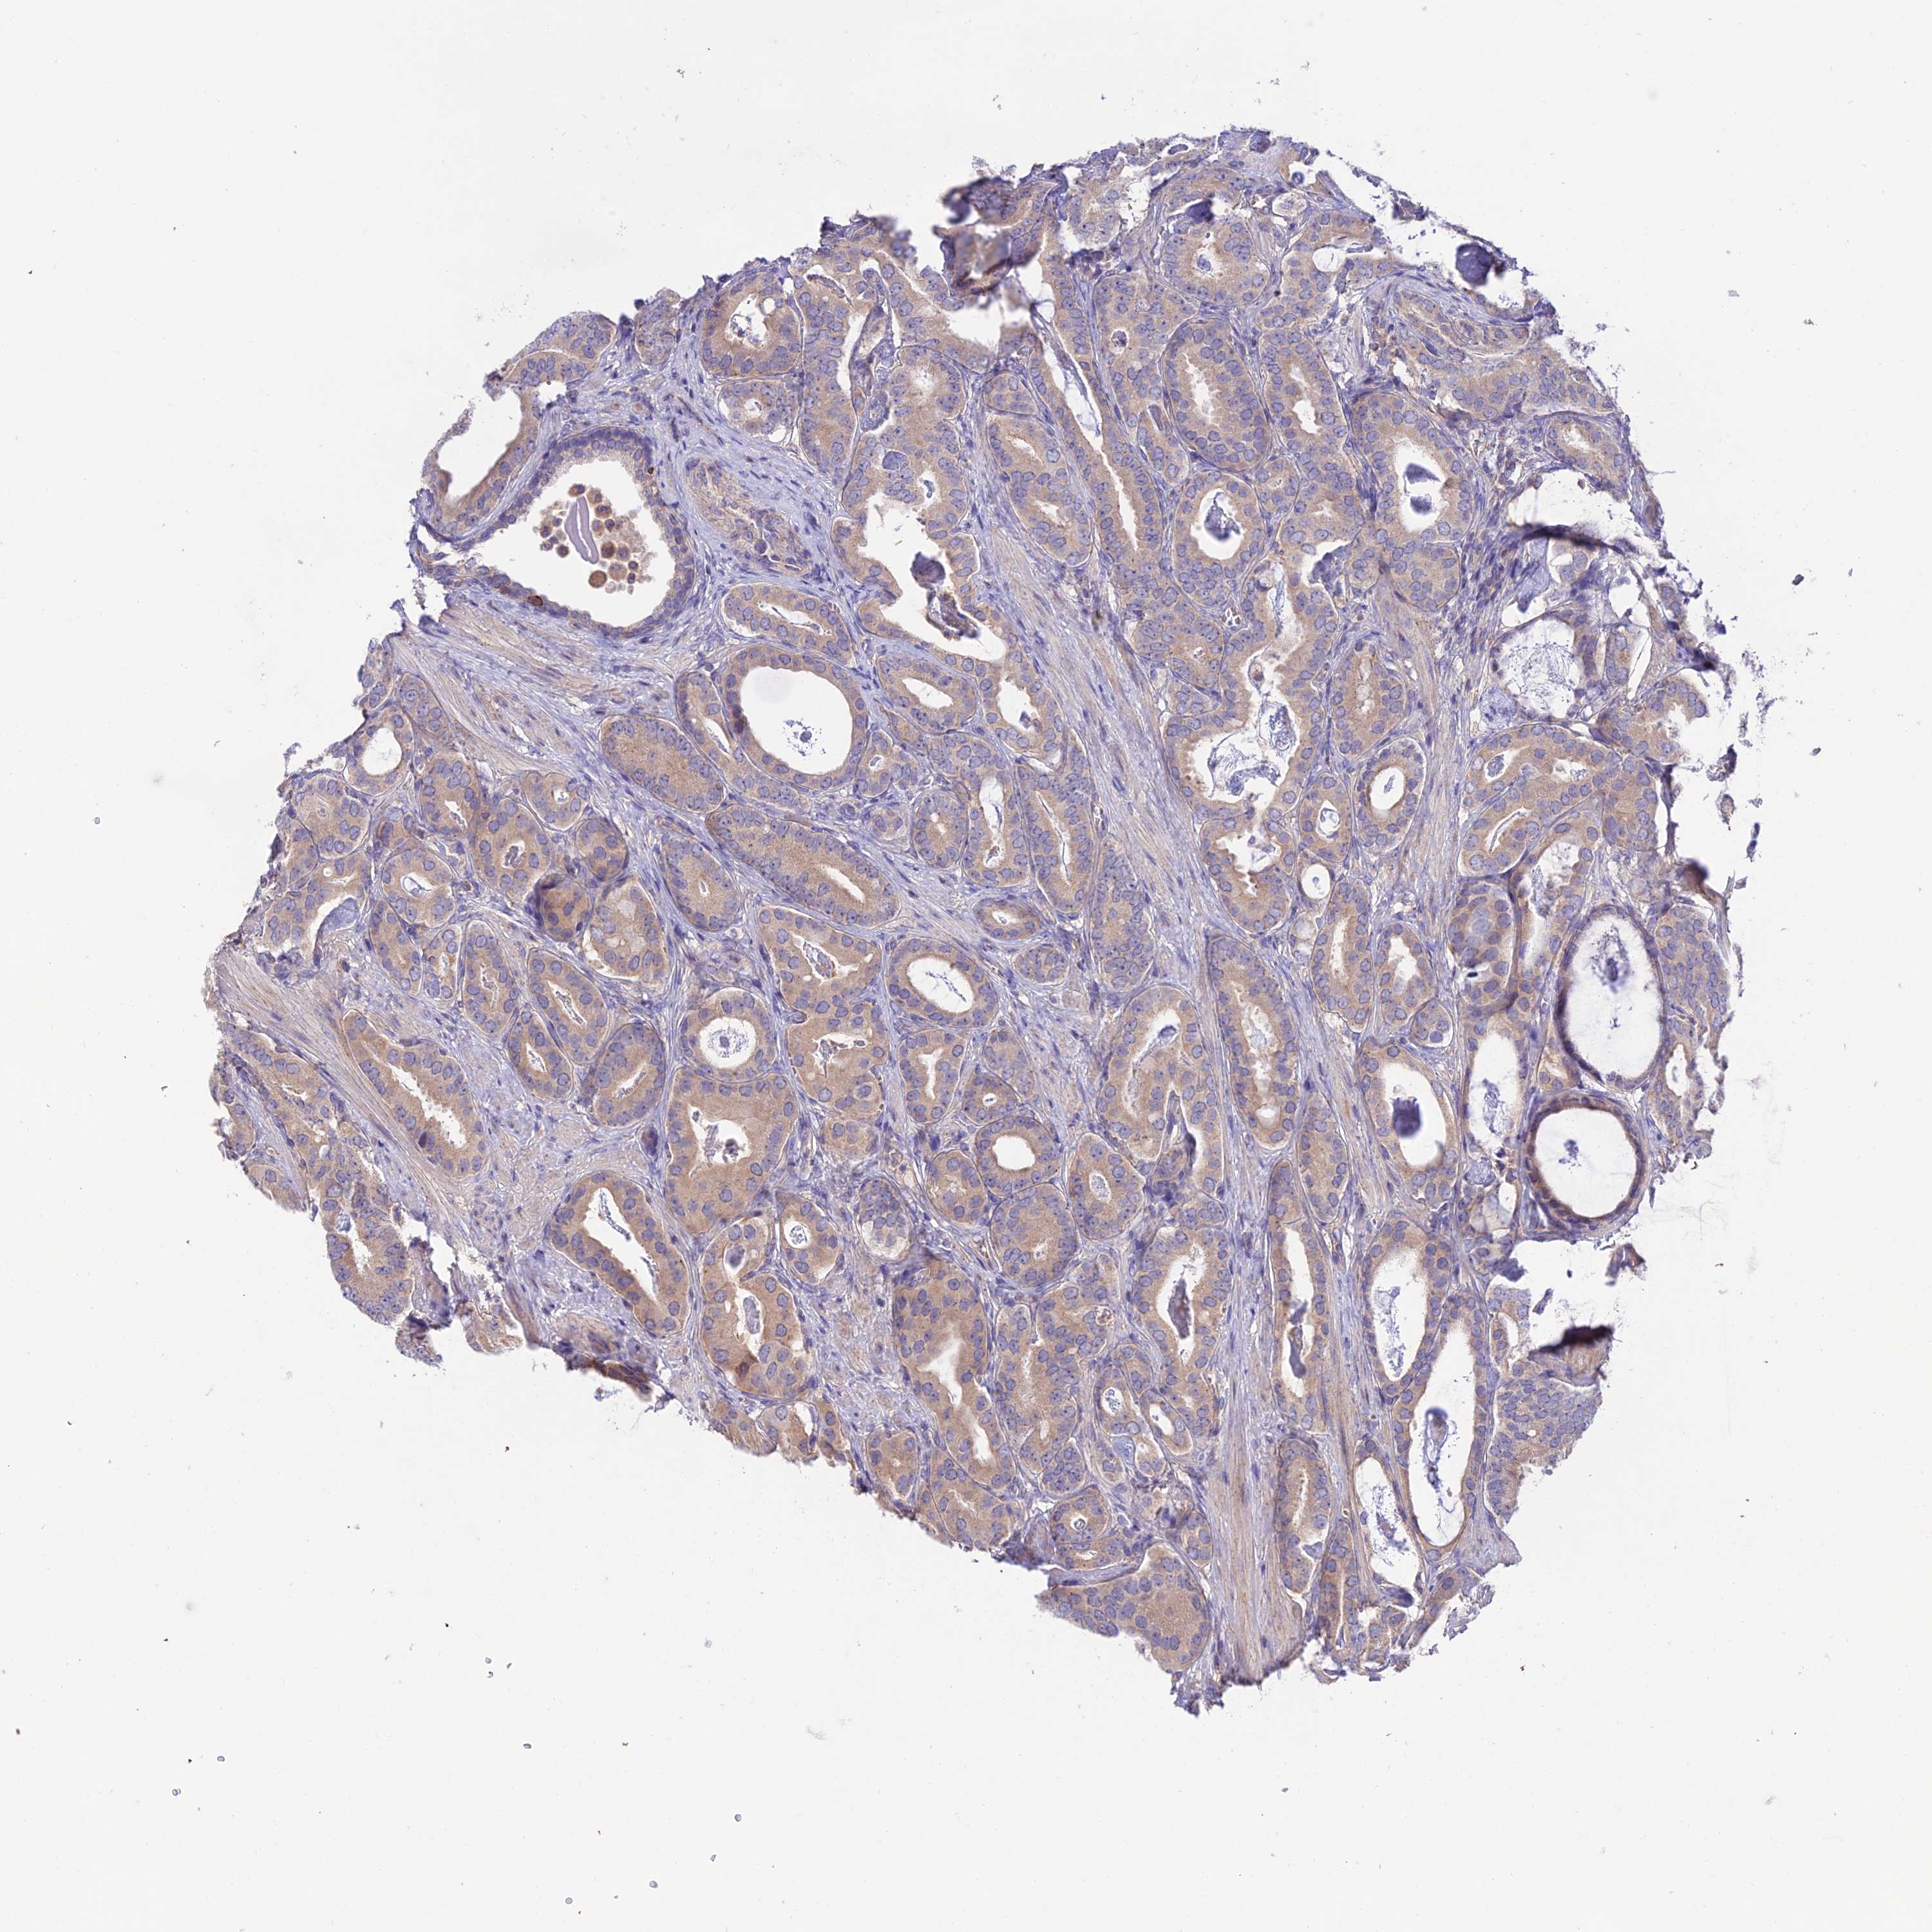

PROSTATE CANCER - Protein expressioni

A mouse-over function shows sample information and annotation data. Click on an image to view it in a full screen mode. Samples can be filtered based on level of antibody staining by selecting one or several of the following categories: high, medium, low and not detected. The assay and annotation is described here.

Note that samples used for immunohistochemistry by the Human Protein Atlas do not correspond to samples in the TCGA dataset.

Antibody stainingi

Antibody staining in the annotated cell types in the current human tissue is reported as not detected, low, medium, or high, based on conventional immunohistochemistry profiling in selected tissues. This score is based on the combination of the staining intensity and fraction of stained cells.

Each image is clickable and will lead to virtual microscopy that enables deeper exploration of all samples and also displays staining intensity scores, fraction scores and subcellular localization as well as patient and tissue information for each sample.

Antibody HPA044012

Staining

High

Medium

Low

Not detected

Intensity

Strong

Moderate

Weak

Negative

Quantity

>75%

75%-25%

<25%

None

Location

Nuclear

Cytoplasmic/membranous

Cytoplasmic/membranous,nuclear

Adenocarcinoma, NOS

Adenocarcinoma, High grade

Adenocarcinoma, Low grade